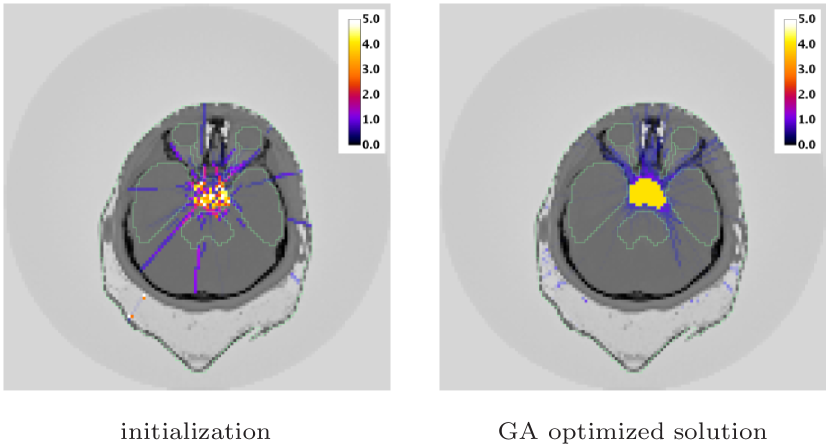

The initial and final dose maps are represented in figure 8 for the slice of the volume, which includes most OAR regions. In the initial dose map, the PTV coverage with beams is not satisfactory and a few beam trajectories pass through OAR regions. In the final dose map obtained with about optimized beams, the dose in the PTV region is almost perfectly homogeneous (the largest deviation from the prescription is ). The algorithm has also found a suitable beam layout, avoiding OARs and limiting the dose to NT.